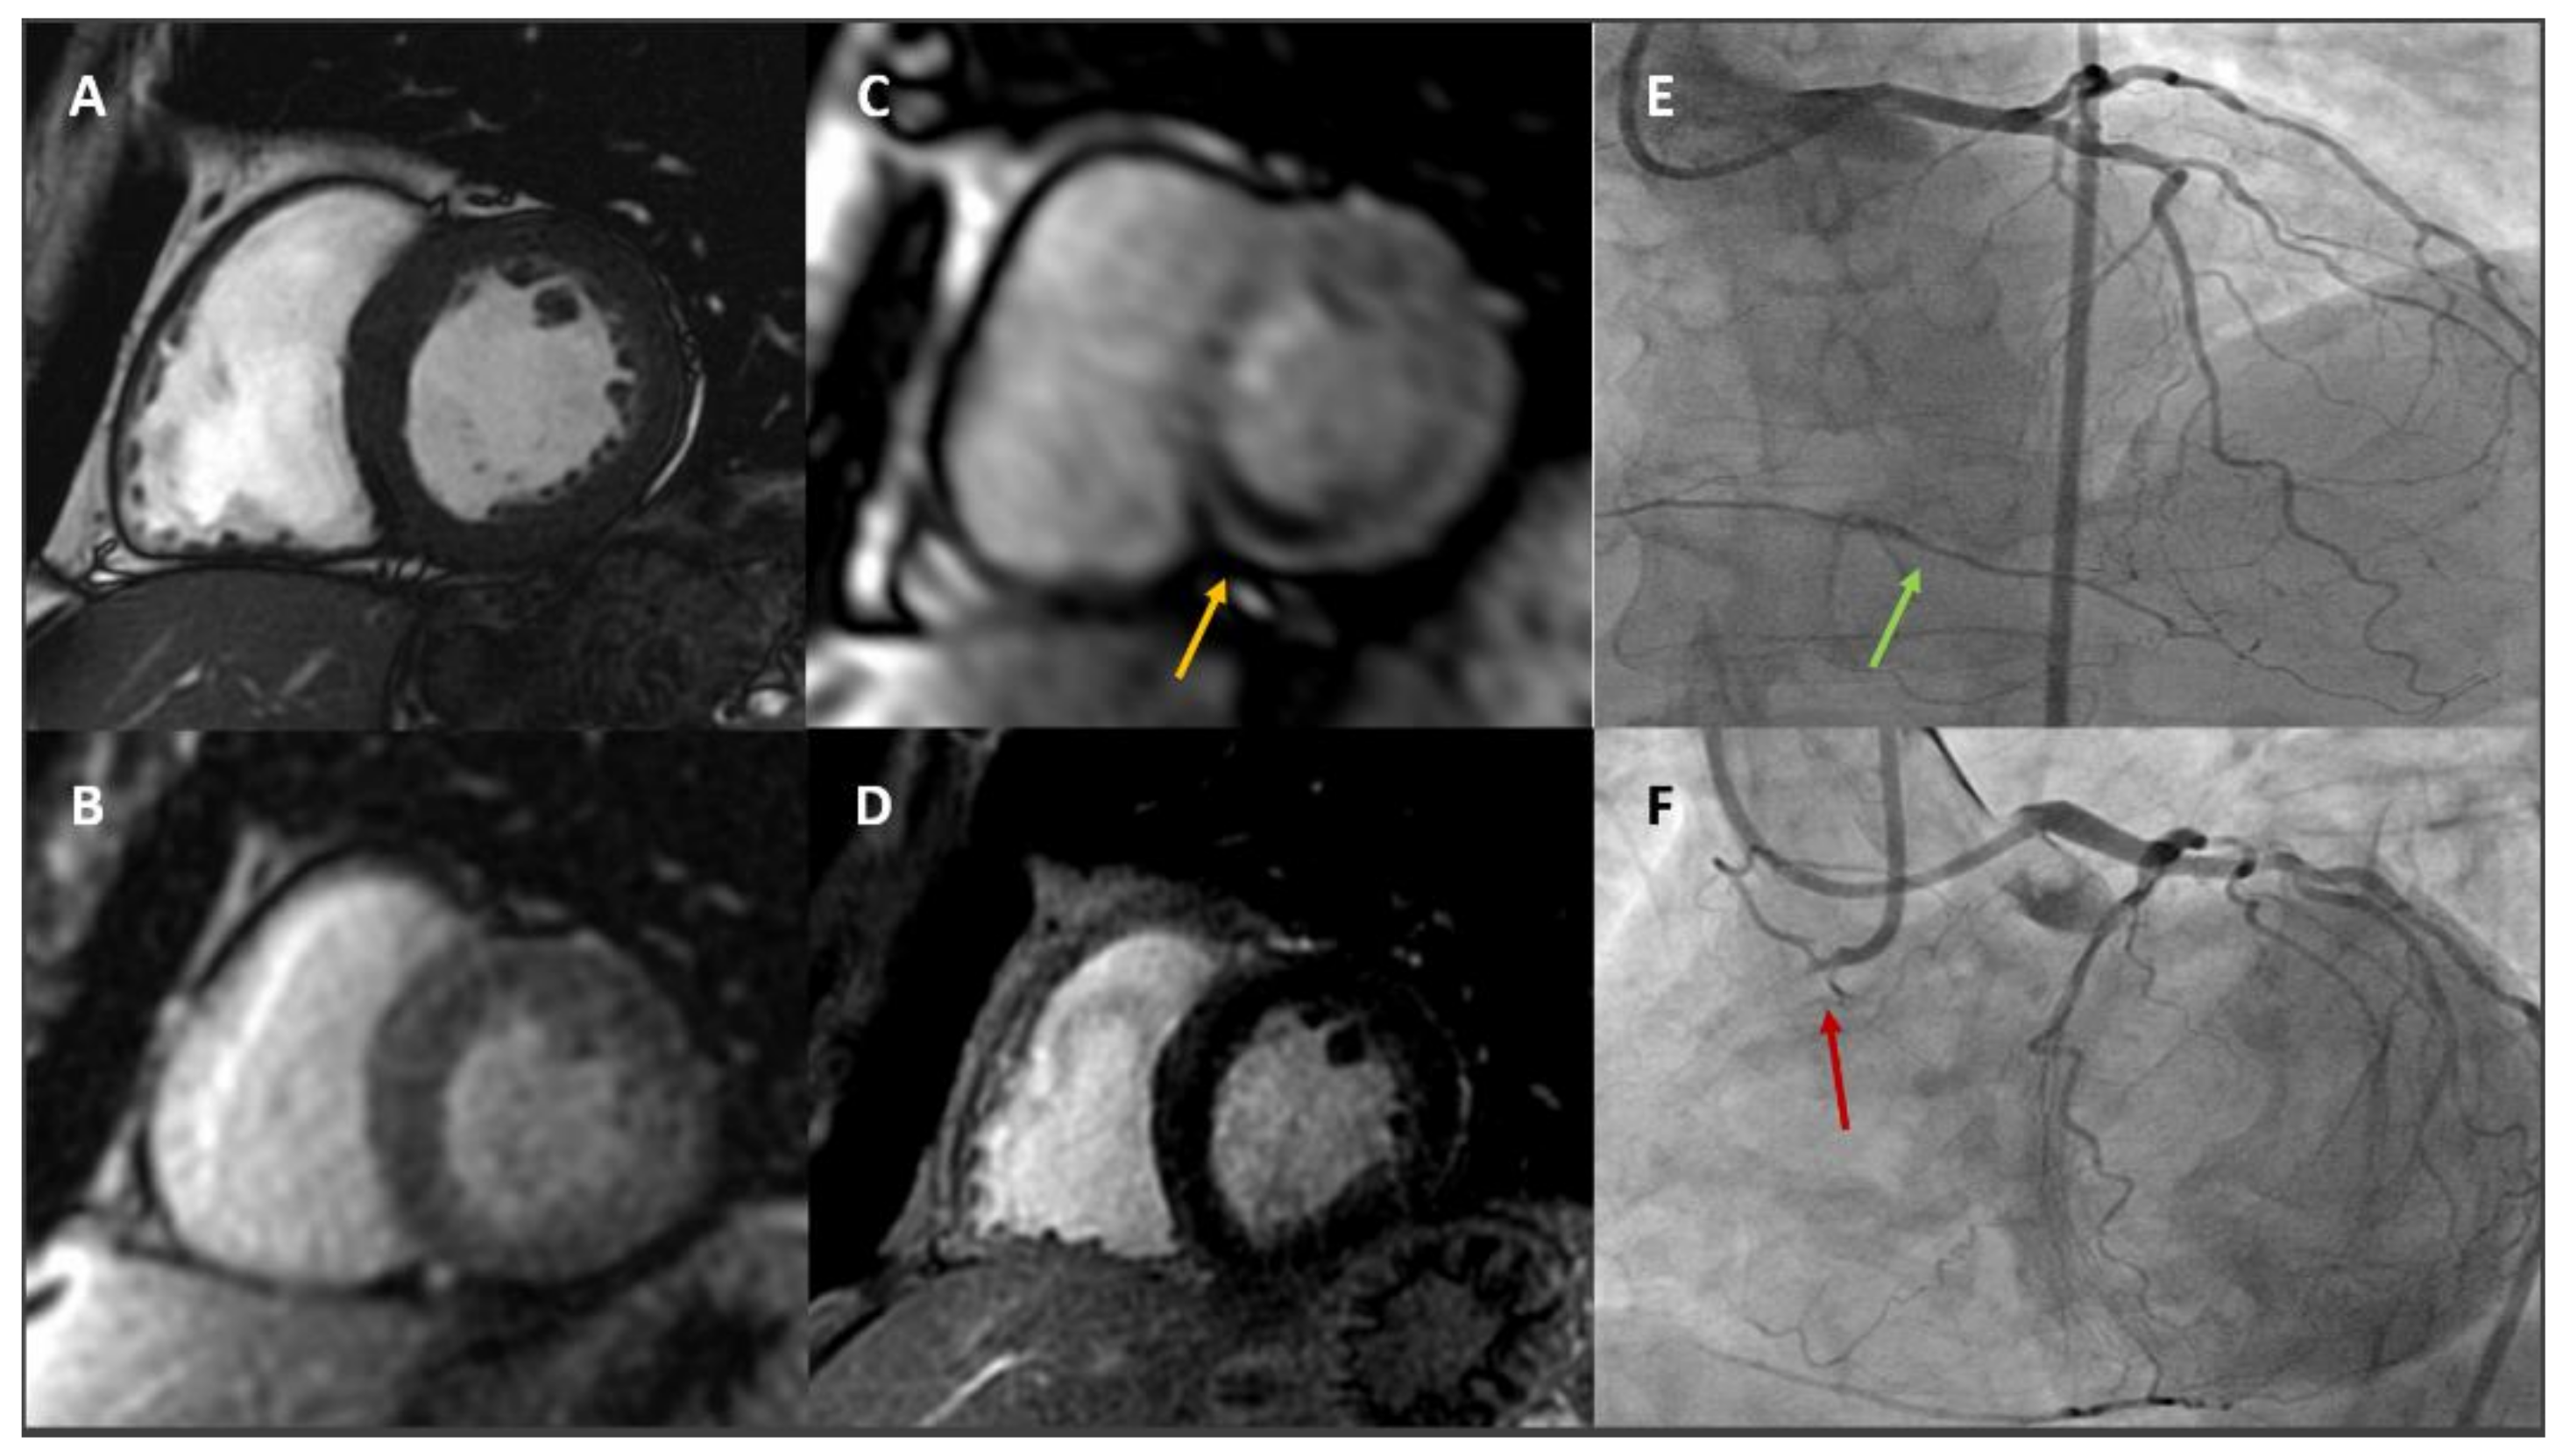

- Baessato, F.; Guglielmo, M.; Muscogiuri, G.; Baggiano, A.; Fusini, L.; Scafuri, S.; Babbaro, M.; Mollace, R.; Collevecchio, A.; Guaricci, A.I.; et al. Stress CMR in Known or Suspected CAD: Diagnostic and Prognostic Role. Biomed. Res. Int. 2021, 2021, 6678029. [Google Scholar] [CrossRef]

- Pontone, G.; Andreini, D.; Bertella, E.; Loguercio, M.; Guglielmo, M.; Baggiano, A.; Aquaro, G.D.; Mushtaq, S.; Salerni, S.; Gripari, P.; et al. Prognostic value of dipyridamole stress cardiac magnetic resonance in patients with known or suspected coronary artery disease: A mid-term follow-up study. Eur. Radiol. 2016, 26, 2155–2165. [Google Scholar] [CrossRef]

- Antiochos, P.; Ge, Y.; Heydari, B.; Steel, K.; Bingham, S.; Abdullah, S.M.; Mikolich, J.R.; Arai, A.E.; Bandettini, W.P.; Patel, A.R.; et al. Prognostic Value of Stress Cardiac Magnetic Resonance in Patients With Known Coronary Artery Disease. JACC Cardiovasc. Imaging 2021, 15, 60–71. [Google Scholar] [CrossRef]